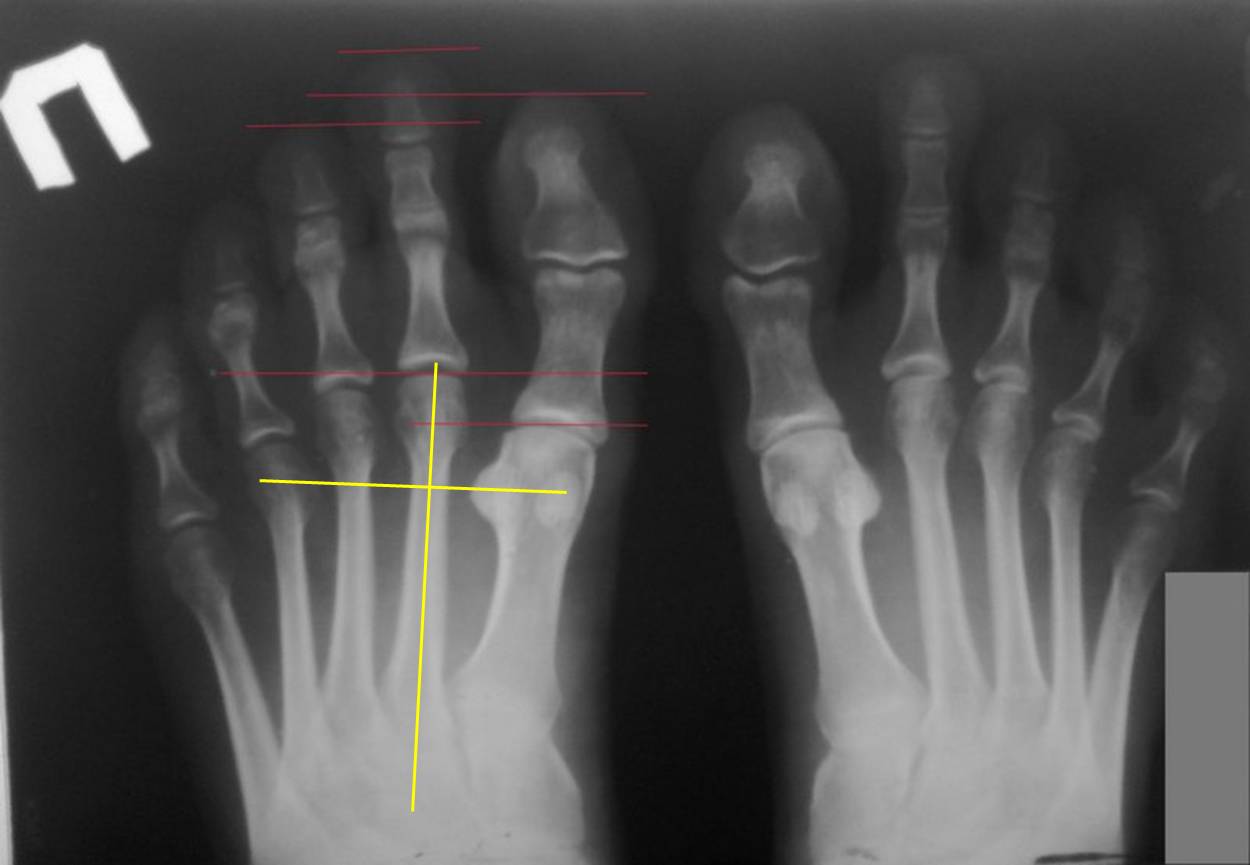

Хорошо, что пациентка отказалась от удлинения 1 плюсневой. Это привело бы к быстрому развитию hallux limitus и артроза. А почему Вы подумали, что 1 плюсневые укорочены? На представленной Вами рентгенограмме я провел перпендикуляр к оси 2 плюсневой кости на уровне середины латеральной сесамовидной. Линия прошла точно через середину головки 4 плюсневой. Это норма. То есть, длины 4 и 5 плюсневых соответствуют длине первой. А вот длины 2 и 3 плюсневых значимо преобладают над длиной первой. В такой ситуации развитие молоткообразной деформации 2 пальца вполне естественно. Есть ли у пациентки натоптыш под головкой 2 плюсневой? Пусть даже и бессимптомный. Если есть, то лучше всего совместить укорочение основной фаланги с остеотомией 2 плюсневой по Вейль. Сама по себе эта остеотомия дает укорочение до 3-5мм. И одновременно позволяет вывести из-под повышенной нагрузки головку 2 плюсневой. Вмешательство на фаланге и плюсневой кости можно делать из одного доступа.